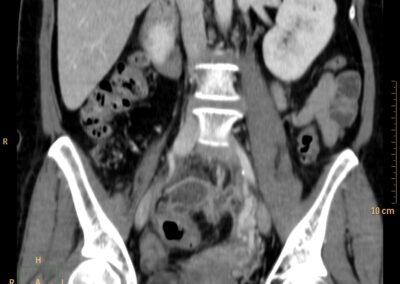

ΕΚΚΟΛΠΩΜΑΤΑ ΠΑΧΕΟΣ ΕΝΤΕΡΟΥ Posted by ΙΠΠΟΚΡΑΤΕΙΟ ΙΩΑΝΝΙΝΩΝ | Dec 16, 2020 | ΠΕΠΤΙΚΟ | 0 ΚΛΙΝΙΚΑ ΣΤΟΙΧΕΙΑ – ΙΣΤΟΡΙΚΟ υποτροπιάζοντες επαναλαμβανόμενοι πυρετοί κυρίως απογευματινές ώρες ΕΡΓΑΣΤΗΡΙΑΚΟΣ ΕΛΕΓΧΟΣ ΑΠΕΙΚΟΝΙΣΤΙΚΟΣ ΕΛΕΓΧΟΣ διακρίνονται τα αποστήματα στην ελάσσονα πύελο, καθώς και εκκολπώματα με εικόνα πάχυνσης του τοιχώματος του σιγμοειδούς ΣΥΖΗΤΗΣΗ